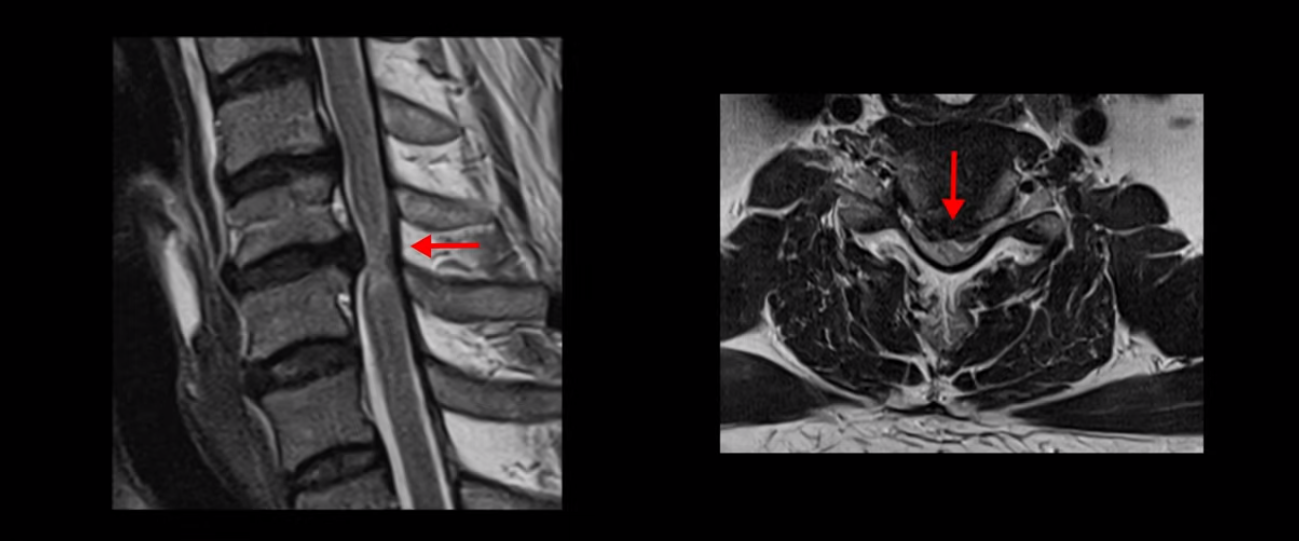

목 5번 6번을 보면 디스크가 심하게 밀려 나와서 척수 신경을 누르고 있습니다.

척수 신경이 눌려서 손상된 사인이 하얗게 보입니다. 이걸 경추척수증이라고 합니다.

척수 신경이 눌리고 손상되니까 양쪽 손과 양쪽 다리 모두에 증상이 생깁니다. 양손에 힘이 빠지고 젓가락질이 힘들고, 단추 끼우기도 어려워지고 다리에 힘이 빠지니까 걷기도 힘들어집니다. 양손과 다리의 감각도 떨어지고요. 그래서 이 환자분은 수술하더라도 목 수술을 해야 하는데, 엉뚱하게도 허리 수술을 받습니다. 처음에 병원에 갈 때 허리도 원래 많이 아팠다고 하니까 그 병원에서 목 검사와 허리를 함께 검사해 보고 허리 협착도 심하니까 허리 수술을 먼저 하자고 합니다. 그래서 허리 세 마디를 수술했습니다.